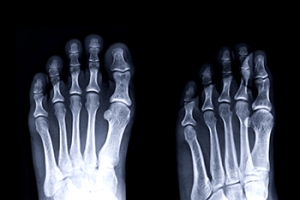

Common symptoms of stress fractures are pain and swelling near the weight bearing area on the injured bone. When initial x-rays are performed, it is possible that the fracture will not show up. However, once the stress on the area continues, the damage will increase, and the fracture will be severe enough to show up on an x-ray. Certain parts of the foot are more likely to develop stress fractures than others. Areas that typically have these fractures are: the metatarsals, the navicular bone, the calcaneus, tibia, and fibula.